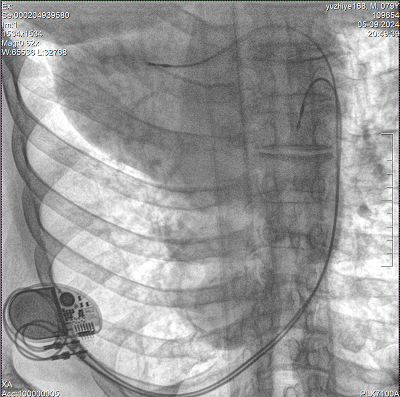

具備血管造影及數(shù)字減影(DSA)、路徑圖(Road-map)、透視、攝影等功能。 廣泛適用于介入科、血管外科、腫瘤科、消化內(nèi)科及骨科等多個臨床科室,典型應(yīng)用包括:TACE(肝腫瘤栓塞與化療灌注術(shù))、心臟起搏器置入術(shù)、四肢動脈造影術(shù)、下肢靜脈濾器置入術(shù)、ERCP(經(jīng)內(nèi)鏡逆行胰膽管造影術(shù))等。